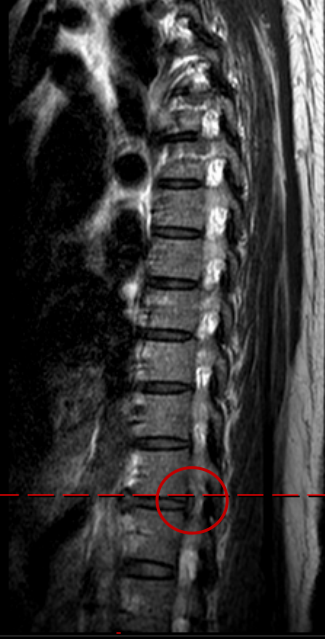

前一阵,她前往广医三院脊柱外科就诊。接诊的主任医师王簕询问完病史后,又为她做了详细的检查,结果发现她的疼痛性质和典型的腰椎源性疼痛不太一样——疼痛位置更固定,且伴随的不适感与腰椎病变的常见表现有明显区别。王簕判断其病根或许不在腰椎,可能在更高位的胸椎,于是为她安排了胸椎磁共振(MRI)检查。

检查结果证明,李女士的胸11/12节段右侧椎间孔处有一块突出的椎间盘组织,恰好压迫到了神经根,这正是导致她一年来反复腰痛的“真凶”——胸椎间盘突出症。

检查结果显示,李女士胸11/12节段右侧椎间孔处发现一突出的椎间盘。